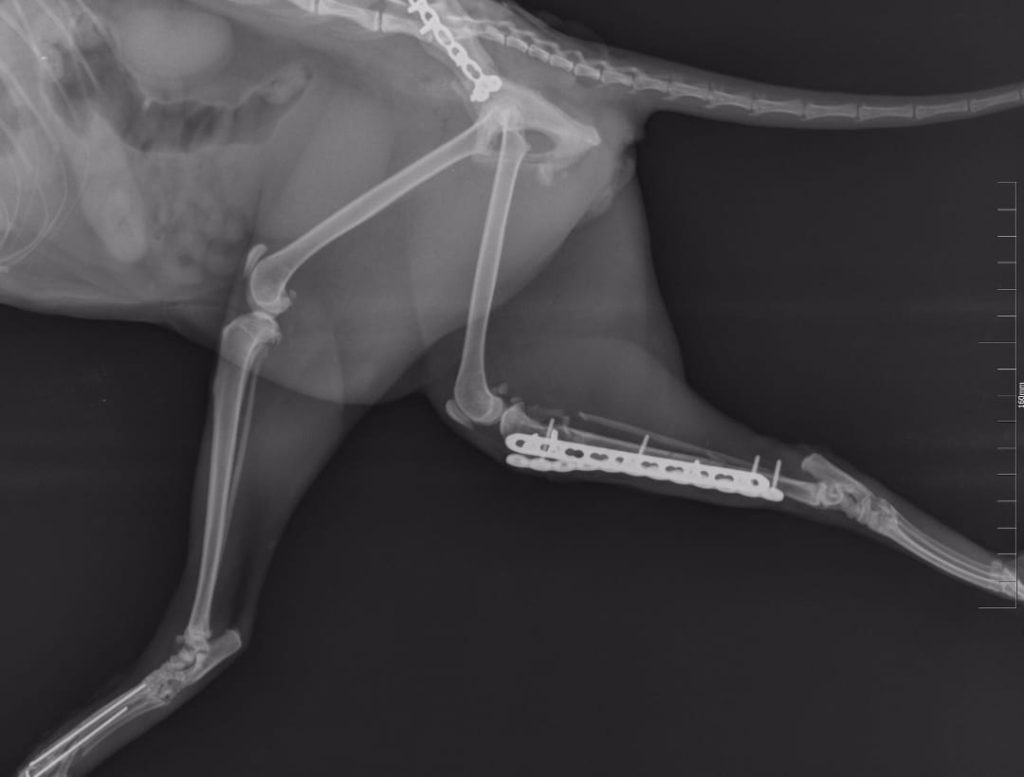

Pisică europeană cu traumatisme provocate prin cădere de la înălțime. Pe măsură ce temperaturile cresc și geamurile rămân deschise mai frecvent, astfel de accidente devin tot mai întâlnite. Indiferent de sezon, este esențial ca proprietarii să fie vigilenți atunci când aerisesc locuința, întrucât o astfel de căzătură poate avea consecințe grave.

În acest caz, examenul radiologic a evidențiat o fractură de paletă iliacă și o desmorexie sacro-iliacă. Ambele leziuni au necesitat intervenție chirurgicală, iar stabilizarea a fost realizată cu plăcuță și șuruburi special adaptate anatomiei feline.

Procedura s-a desfășurat cu succes, restabilind continuitatea structurilor osoase și oferind pacientului condițiile optime pentru o recuperare completă.